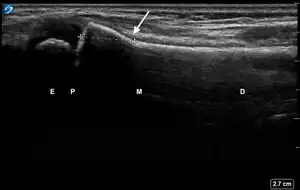

![]() Ultrasound lateral view of normal radius. E = epiphysis; P = physis; M = metaphysis; D = diaphysis. | |

| 2 | Buckle (Torus) Fracture | "Bent" | ![]() Ultrasound dorsal view of buckle fracture of radius (shown by arrow). E = epiphysis; P = physis; M = metaphysis; D = diaphysis. | ||